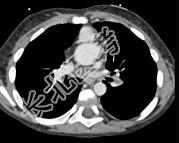

- 多项选择题患者,男性, 8岁,发绀、气促, 易感冒,彩超提示只见一个心室, CT检查如图所示,请选择正确的选项 ( )